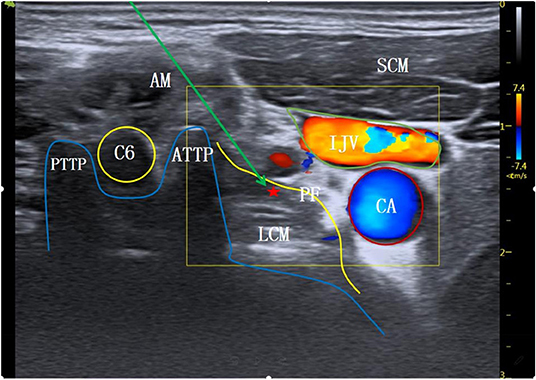

Stellate Ganglion cross section

A

Stellate Ganglion Block

5 mL